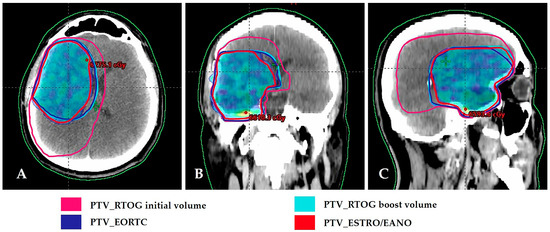

| Group | Definition | CTV-Initial | CTV-Boost | PTV |

|---|---|---|---|---|

| ABTC | Two-phase: 46 + 14 = 60 Gy | T2 + T1E + resection cavity + 5 mm | Resection cavity + T1E + 5 mm | 5 mm |

| EORTC | Single-phase | Resection cavity + T1E + 2 cm | - | 5 mm |

| NCCTG/Alliance | Two-phase: 50 + 10 = 60 Gy | T2 + T1E + resection cavity + 20 mm | Resection cavity + T1E + 20 mm | - |

| RTOG/NRG | Two-phase: 46 + 14 = 60 Gy | T2 +T1E + resection cavity + 20 mm | Resection cavity + T1E + 20 mm | 5 mm |

| ESTRO/EANO | Single-phase | Resection cavity + T1E + 15 mm (include non-contrast-enhancing tumor if suspected on FLAIR imaging) | - | 3 mm |